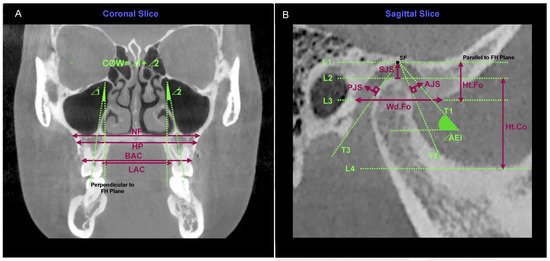

- Draw four parallel lines of FH from the superior to the inferior, tangent to the glenoid fossa, condyle, the lowest end of the articular eminence, and the sigmoid notch of the mandible, respectively, named L1, L2, L3, and L4. The vertical distance between L2 and L4 was defined as the condyle height (Ht.Co) and the vertical distance between L1 and L3 was defined as the fossa height (Ht.Fo). L3 intersected the posterior wall of the fossa, and the horizontal distance between the intersection point and the tangent point was defined as the fossa width (Wd.Fo).

- Taking the tangent point of L1 (superior fossa (SF) point) as the starting point, draw three new tangent lines from the anterior to the posterior, which were tangent to the posterior slope of the articular eminence, the anterior edge of the condyle, and the posterior edge of the condyle, respectively, named T1, T2, and T3. The angle between T1 and FH was defined as the articular eminence inclination (AEI).

- Joint spaces were measured using the Kamelchuk method [66]. The distance between the tangent point of L1 and L2 was measured as the superior joint space (SJS). The perpendicular distance from T2 tangent point to the posterior slope of articular eminence was defined as anterior joint space (AJS), and the perpendicular distance from T3 tangent point to the posterior wall of fossa was defined as posterior joint space (PJS).